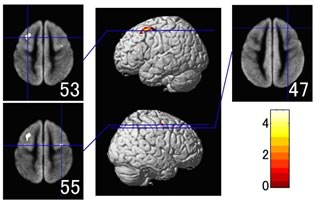

収縮期血圧(値が大きい方)が高くなると、後頭葉に黄色で示した小さな場所に萎縮が見つかります。飲酒も脳萎縮の原因になっているようです。飲酒量が多い人ほど、前頭葉上部の中前頭回と呼ばれる場所に大きな萎縮が見つかります。

お酒をたくさん飲むと、前頭葉上部が萎縮します(数字は脳断面のレベル)黄色に見えるところが、より萎縮の進んでいるところ